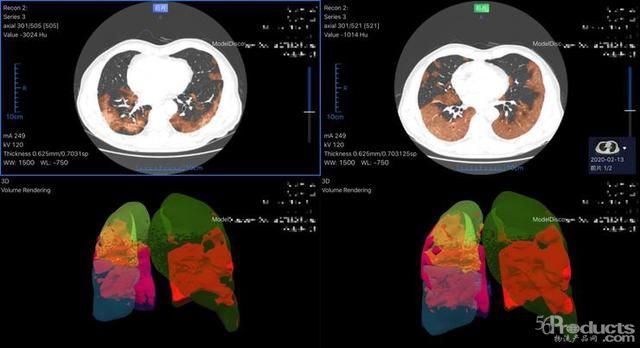

以最早進(jìn)入武漢一線的數(shù)坤新冠肺炎人工智能影像輔助診斷系統(tǒng)為例,面對300-500層胸部圖像,系統(tǒng)可在2-3秒內(nèi)自動完成肺部感染區(qū)域體積、密度、分期等多個臨床指標(biāo)的計(jì)算,為危重患者的搶救贏得寶貴時間。

1.jpeg

數(shù)坤AI在武漢一線醫(yī)院使用